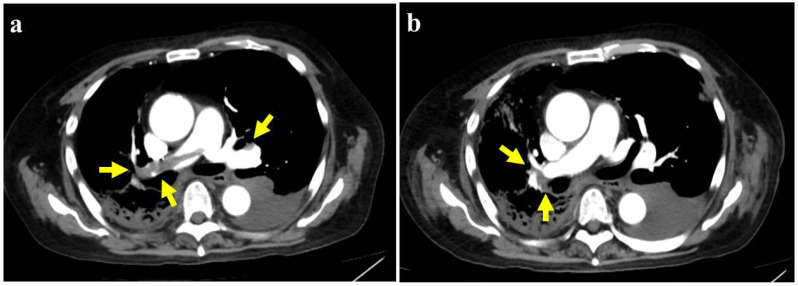

Olaparib, a poly (ADP-ribose) polymerase (PARP) inhibitor approved for treating metastatic castration-resistant prostate cancer (mCRPC) with BRCA mutations, has significant clinical benefits. However, evidence suggests an increased risk of venous thromboembolism, including pulmonary embolism (PE), particularly in patients with PC. However, no case reports of olaparib-associated PE in mCRPC have been published. Here, we report the case of a 70-year-old man with mCRPC harboring a BRCA2 mutation, who developed PE during olaparib therapy. Diagnostic evaluations included contrast-enhanced computed tomography and serum D-dimer level measurement. Clinical decision tools, such as the Wells score and the Khorana score, were used to support the diagnosis and risk assessment. The patient developed acute dyspnea and chest pain 7 months after olaparib initiation. Imaging confirmed multiple pulmonary emboli; laboratory testing revealed markedly elevated D-dimer levels. Anticoagulation therapy with apixaban led to rapid clinical and radiological improvement. However, mCRPC eventually progressed after olaparib discontinuation, and the patient died 15 months after olaparib initiation. This is the first reported case of olaparib-associated PE in mCRPC. It underscores the importance of vigilance for thromboembolic complications during PARP inhibitor therapy. The integration of clinical scoring systems and biomarkers may facilitate timely PE diagnosis and management, potentially improving patient outcomes.